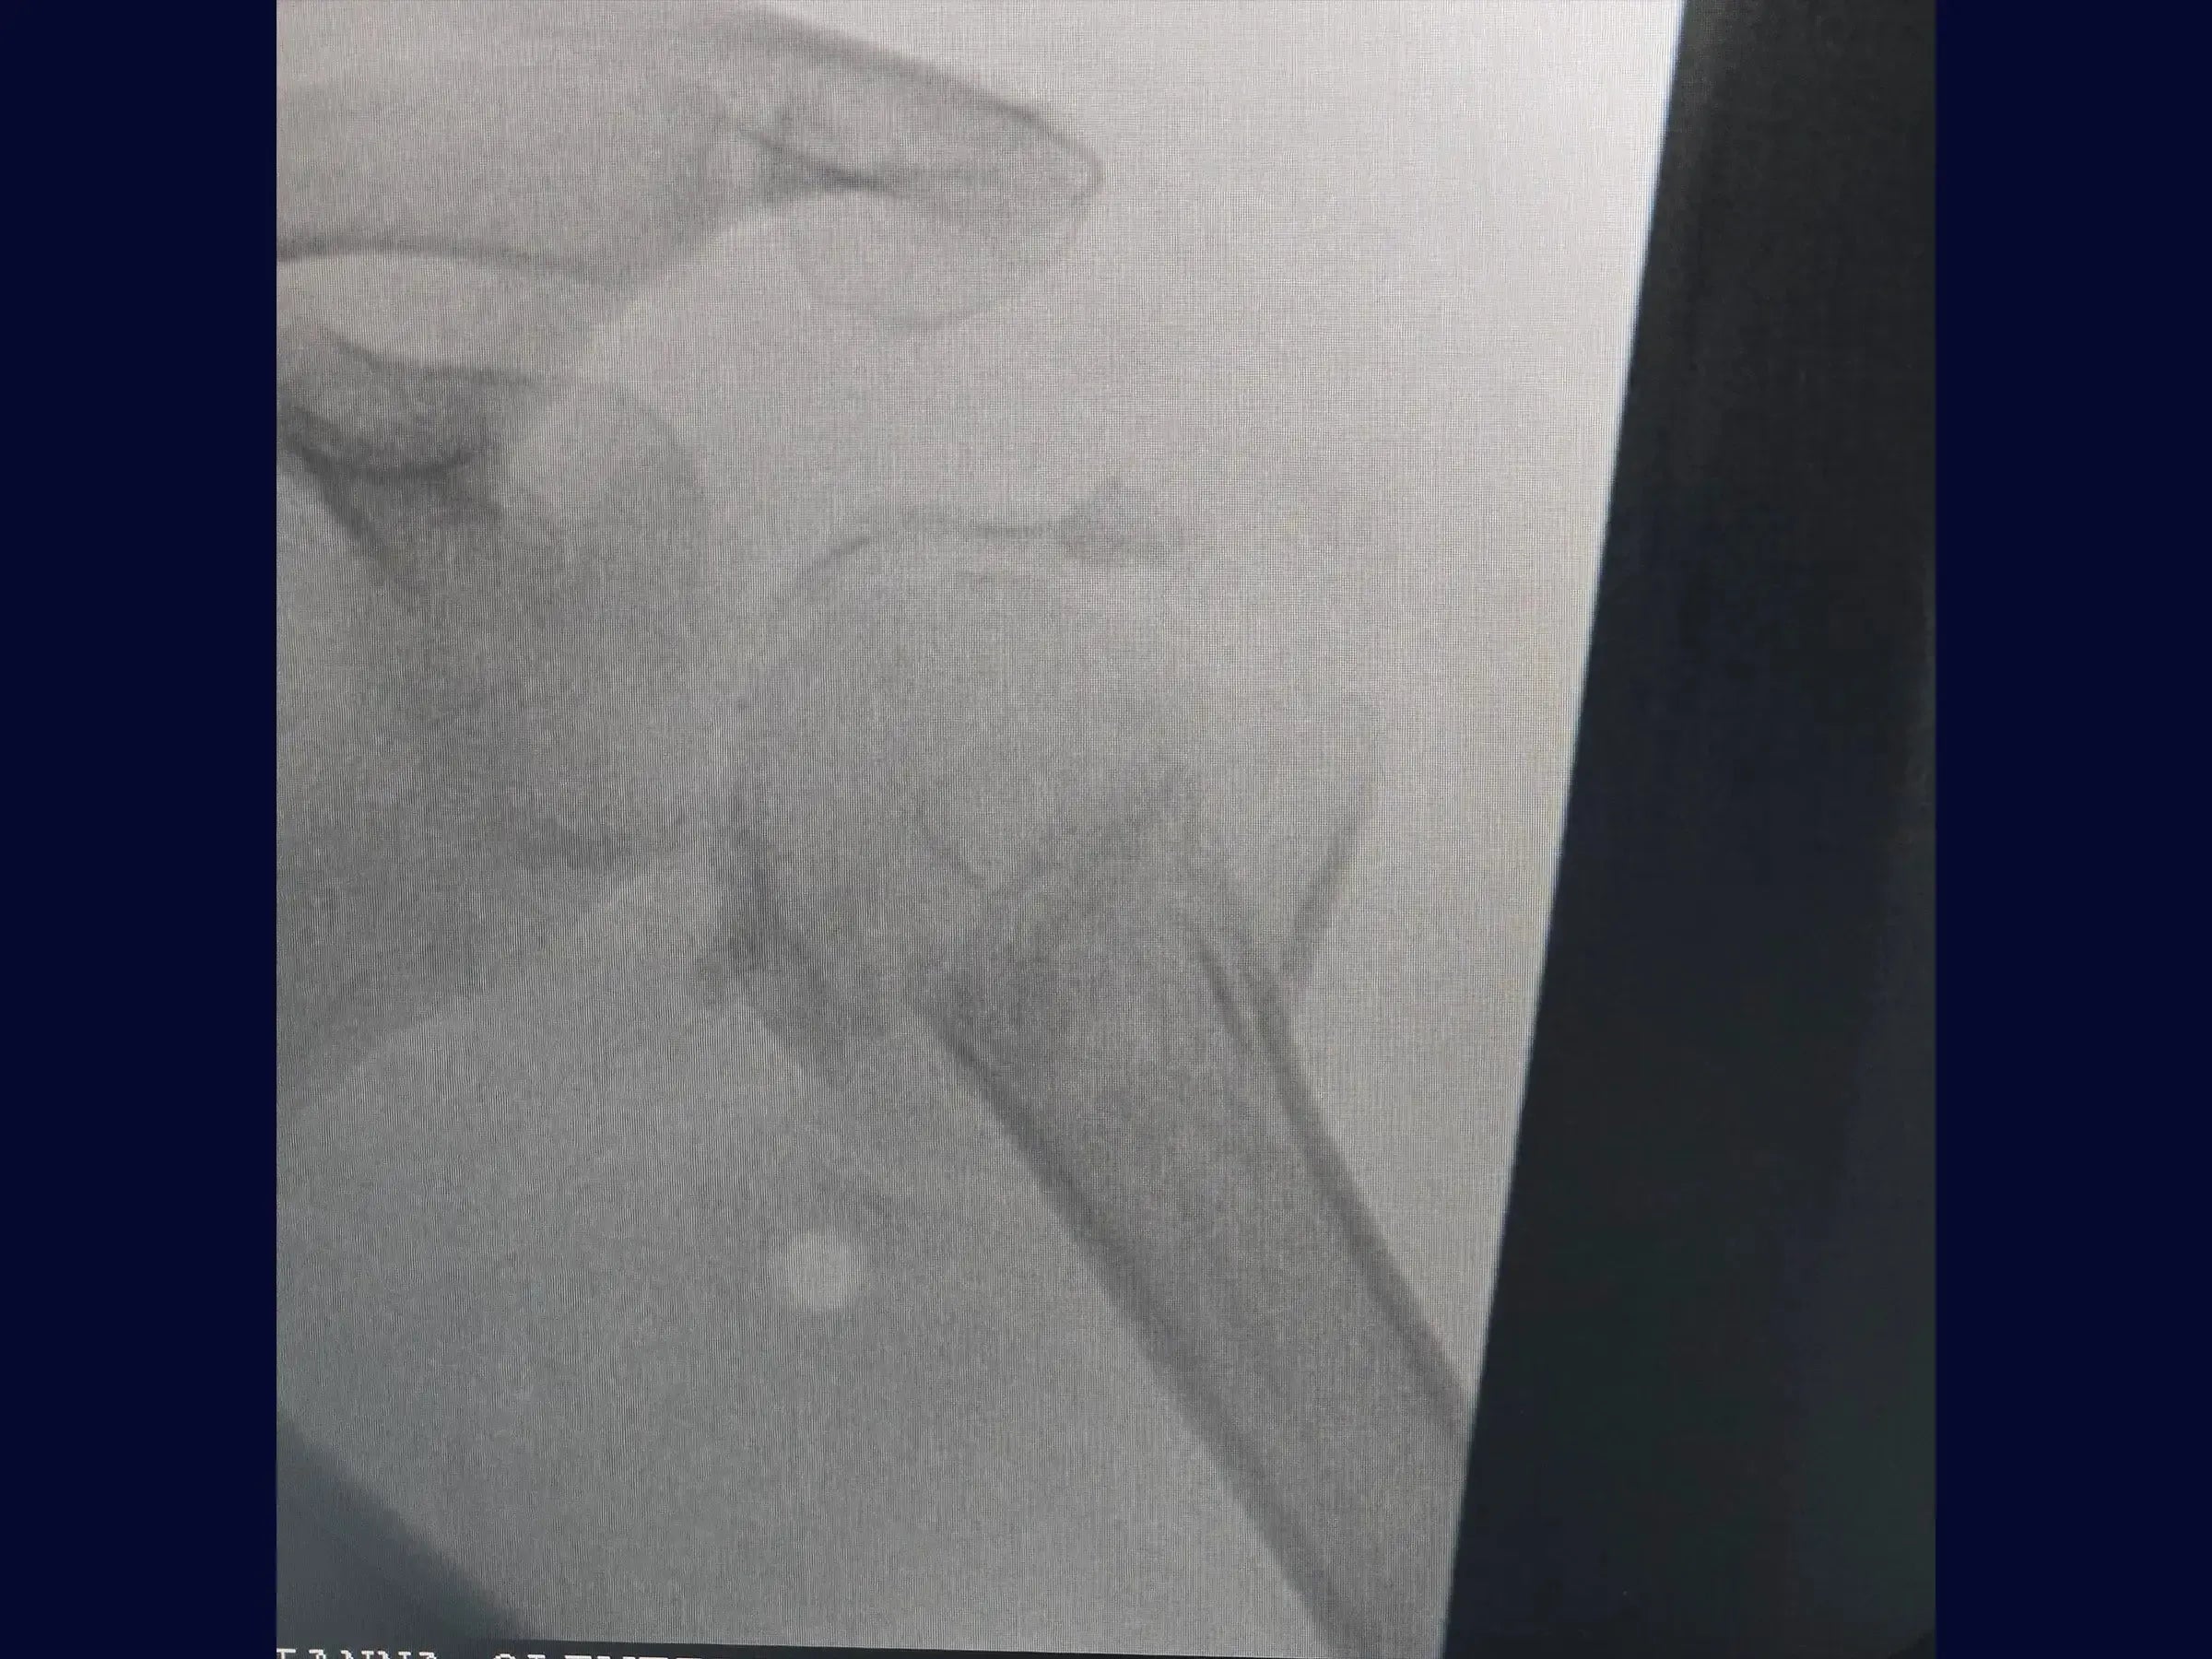

Reconstrução de Fratura Complexa em Quatro Partes do Úmero Proximal

Domine o tratamento de fraturas complexas do úmero proximal. Este treinamento oferece uma imersão técnica na reconstrução de fraturas em quatro partes, com ênfase na abordagem deltopeitoral e fixação com placa e amarrilhas, apresentada em vídeo 4K sob a perspectiva do cirurgião.

- Reconstrução de fraturas complexas em quatro partes do úmero proximal.